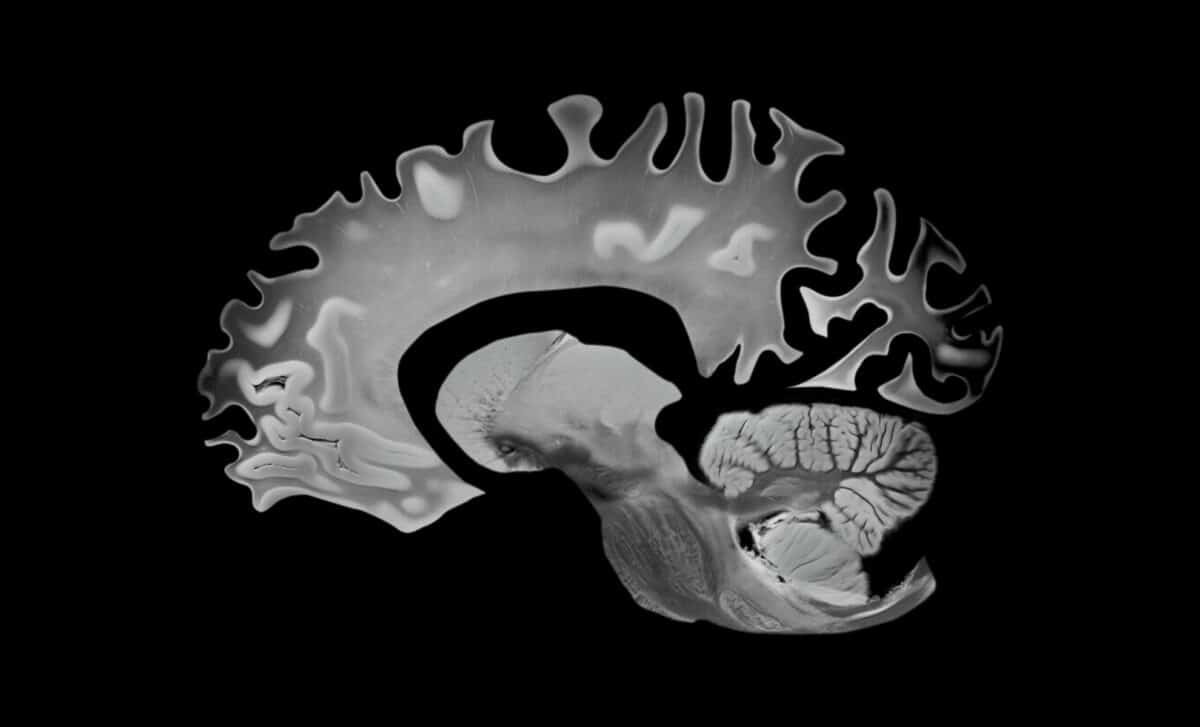

During a median follow-up of 12.3 years, researchers discovered that stricter adherence to the MIND diet corresponded with a slower decrease in total gray matter volume. Specifically, a three-point increase in MIND diet scores related to a 0.279 cm³/year reduction in gray matter loss—a significant 20.1% slowdown in age-related decline, effectively translating to about 2.5 years less brain aging over the study’s duration.

But the implications extend beyond just gray matter. Higher adherence to the MIND diet was also linked to a slower increase in lateral ventricular volume, indicating brain tissue loss, which led to an 8% to 8.8% reduction in age-related changes—about one year of postponed brain aging during the follow-up.

To grasp why these results are significant, it’s important to consider the biological stakes. Gray matter, which contains a high concentration of neuronal cell bodies, dendrites, and synapses, is essential for functions like memory and decision-making. On the other hand, the expansion of ventricles signifies brain atrophy, with tissue loss resulting in increased cerebrospinal fluid-filled spaces.

Essentially, both markers tracked in this study are recognized indicators that the brain is shrinking in ways that can lead to cognitive decline.